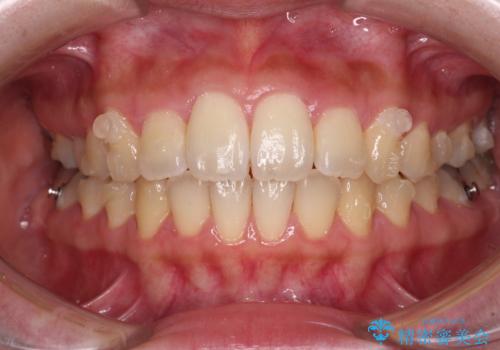

- 捻れた前歯が飛び出しており、口が閉じにくいとのことで来院された患者様です。

出っ歯というわけではないものの、前歯の捻転により口唇が押し出されている状態でした。

親知らずを抜去し、歯列全体を後方に移動させつつ、IPR(歯と歯の間を削る)でスペースを獲得し、インビザラインを用いて叢生を解消しながら前歯の突出を改善することとしました。

インビザラインは、患者様の協力無しには成立しない治療ですが、しっかりと装着時間を遵守してくださり、1年弱で治療を終えることができました。